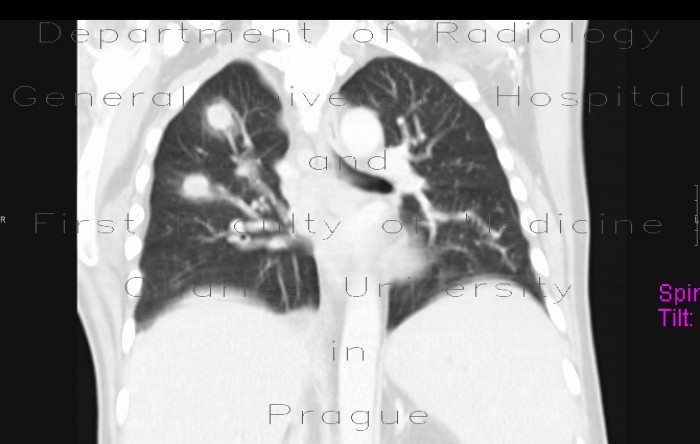

Pulmonary Involvement In Pediatric lymphoma

Introduction Before the current era of computed tomography (CT), pulmonary parenchymal involvement with lymphoma was reported in 11.6% of patients with Hodgkin disease ... Return Document

Primary Pulmonary lymphoma - Orphanet

Primary pulmonary lymphoma (PPL) is defined as a clonal lymphoid proliferation affecting one or both lungs (parenchyma and/or bronchi) in a patient with no detectable extrapulmonary involvement at diagnosis or during the subsequent three months. ... Fetch Full Source